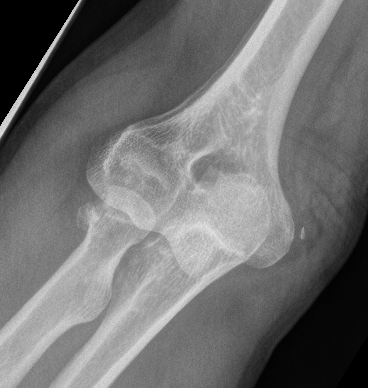

Elbow dislocation with coronoid process fracture

Elbow Dislocation Large Coronoid Fragment

Coronoid process

Coronoid is the most important portion of ulno-humeral articulation

- provides anterior buttress

- attachment of capsule and brachialis

- anterior band of the MCL attaches to it